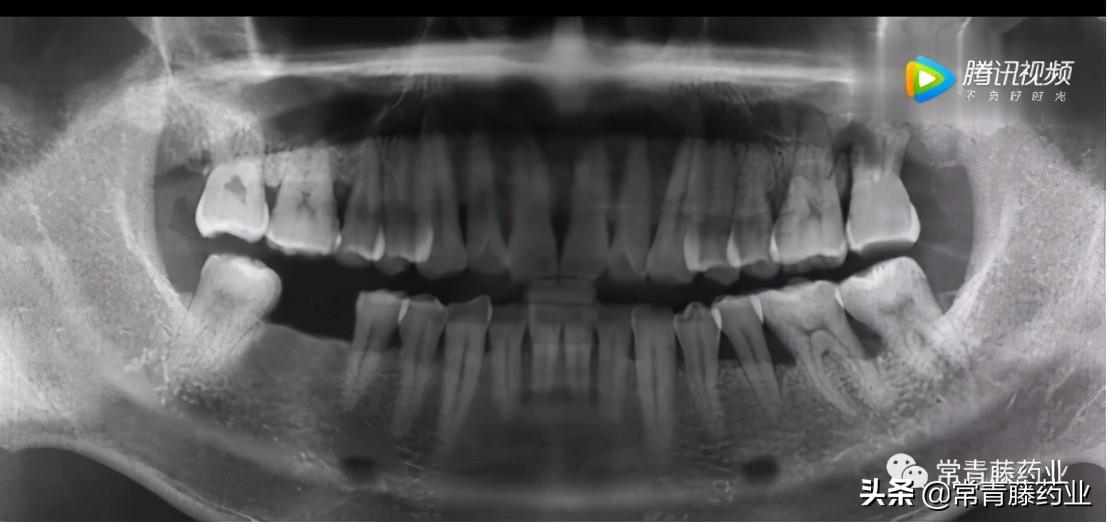

今天給大家科普一下種牙的知識!在種牙開始之前需要進行口腔檢查和全景片、頜骨CT拍攝以確定牙周是否有炎癥、牙槽骨頭是否擁擠以及牙體情況等。(如下圖)